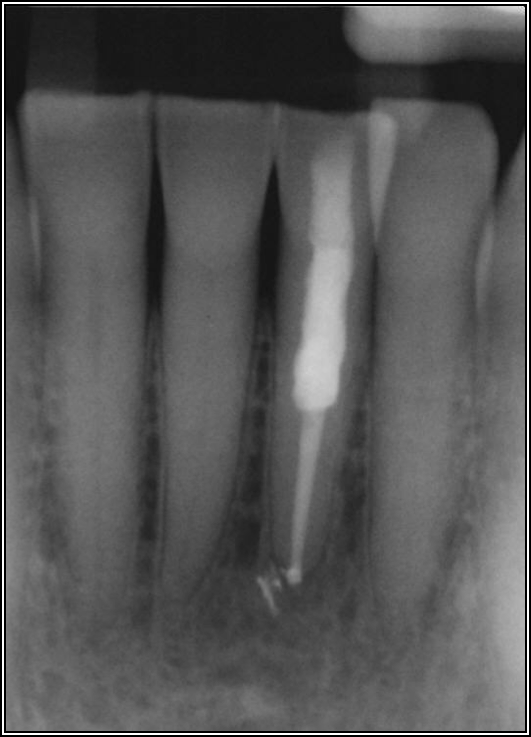

As to which material to use, the literature indicates fiber is better because it has greater flexibility and is less likely to allow for vertical fractures.2,3 It also has better esthetics, which is significant for both anterior and posterior teeth. The problem with fiber posts is that they can snap off and pull out. When they snap off, they are difficult to remove. A tapered diamond bur or ultrasonic can be used, but it must be done very carefully. Depending on the circumstances, metal can also be difficult, but metal is often serrated or threaded and can be unwound with an ultrasonic. However, fiber is significantly more flexible because it has a better modulus of elasticity, which should be as close to the dentin's elasticity as possible. On the radiograph, it can be difficult to see. Figure 17 shows a case with a good fiber post on the lateral that could be longer. The central should definitely be longer than it is. Because the clinician thought the posts and crowns were well done with good seals, when the patient had pain and apical radiolucencies, they were treated with apicoectomies. This was easier and less invasive than dismantling the previous structure.

Fig 17. A case with a good fiber post on the lateral that could be longer.

Figure 17